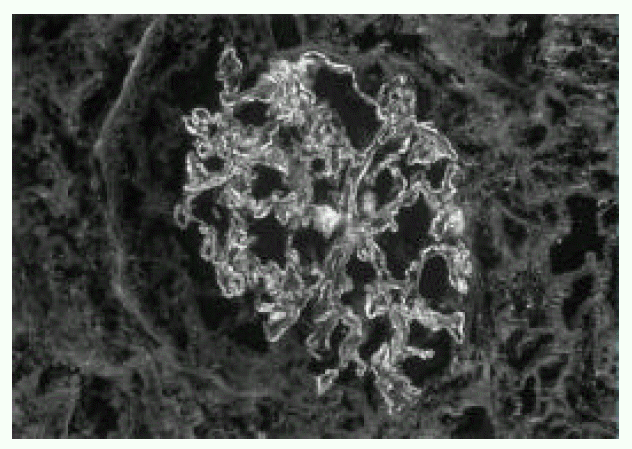

Figure 3.

IF shows a diffuse granular staining with anti-IgG and anti-C3 along the capillary wall

A 66-year-old man was admitted to Keimyung University Hospital because of decreased urine output and right upper quadrant pain. Seven years earlier, he had a Whipple’s operation for obstructive jaundice due to Ampulla of Vater cancer. At that time, the pathology report showed a moderately differentiated adenocarcinoma and biopsies of the regional lymph nodes showed no evidence of metastasis. At that time, renal function was normal and the urine contained no proteins or red cells. Two weeks before admission, the patient developed right upper quadrant dull pain, nausea, anorexia, myalgia, chills and fever. Four days prior to admission, he noticed gross hematuria, marked decrease in urine output and edema in lower extremities. On admission, his body temperature was 36.4°C and blood pressure was 110/60 mmHg. Daily urine output ranged 800–1200 mL. Face was puffy. He did not have icterus. His conjunctivae was slight anemic and revealed several petechial hemorrhages. Auscultation of the lung revealed bilateral basilar rales. No murmurs or frictions were heard. The liver was enlarged and tender. There was no splenomegaly or rash. There was marked costovertebral angle enderness. here was mild pretibial edema. Laboratory data on admission showed WBC 34,600/mm3, hemoglobin 8.3 g/dL, platelet count 95,000/mm3, BUN 16.4 mmol/L, serum creatinine 985,6 μmol/L, cholesterol 118 mg/dL, total bilirubin 3.4 mg/L, alkaline phosphatase 270 IU/L, SGPT 18 IU/L, and serum albumin 2.0 g/dL and creatinine clearance 2.5 ml/min. Urinalysis showed specific gravity 1.020, protein 2+, and urinary sediment containg two granular casts, many red blood cells and 10 white blood cells/HPF. The 24-hour urinary protein excretion was 2.4 gm and FENa was 1.7%. C3 level was 0.67 g/L (normal range: 0.8–1.2 g/L) and C4 level was 0.46 g/L (normal range: 0.2–2.5 g/L). Cryoglobulin was absent. The tests for hepatitis B and C, antinuclear antibody and rheumatoid factor were negative. Chest radiographs demonstrated bilateral perihilar pulmonary congestions. On admission, he was afebrile. He had obvious pulmonary edema as well as peripheral edema. Immediate hemodialysis resulted in a weight loss of 2 kg and respiratory improvement. Ultrasonographic examination of liver showed ill marginated cystic mass in left lobe. Computed tomography (CT) of the abdomen demonstrated 7×5cm sized multiple septated lower density lesions in medial segment of left lobe of the liver (Figure 1). Numerous blood cultures were negative. Initially the patient was treated with diuretics, albumin infusions and antibiotics (sulbactam/cefoperazone and aztreonam). On the 15th day, percutaneous needle biopsy of the kidney was performed. Light microscopy showed 17 glomeruli with two global sclerosis. The glomeruli showed endo-and extracapillary proliferation (Figure 2), with cellular crescents involving 25% of the glomeruli. The interstitium showed diffuse edema and no tubular necrosis. Immunofluorescent examination showed a diffuse granular staining with anti-IgG and anti-C3 along the capillary wall, and no staining with anti-IgM or anti-IgA (Figure 3). Needle aspiration of the liver was performed on the 19th hospital day, with the drainage of greenish pus material. Culture of the liver aspirates later grew Pseudomonas aeruginosa. Ticarcillin was given. The patient improved substantially. The levels of BUN and serum creatinine declined progressively and stabilized at 5.7 mmol/L and 176 μmol/L, respectively, by the 25th hospital day. One month after admission, the laboratory findings were : BUN 5.5 mmol/L, serum creatinine 176 μmol/L, hemoglobin 8.1g/dL. WBC 5,430/mm3 and platelet count 208,000/mm3. The 24-hour urinary protein excretion was 4.4 g/day. Follow-up CT showed almost complete resolution of previous abscess in the liver. He was discharged on the 40th hospital day with the serum creatinine level of 167 μmol/L.

There has been no reported case of glomerulonephritis in association with pyogenic liver abscess in a large series of visceral infection-associated glomerulonephritis according to a comprehensive review of literature by Coleman et al8). There has been only one report of solitary pyogenic liver abscess with associated glomerulonephritis in a neonate9). Thus, our case may be the first report documenting the occurrence of glomerulonephritis associated with the pyogenic liver abscess in a adult. A variety of bacteria have been implicated. Pseudomonas aeruginosa was the responsible organism in our case and 2 out of 8 cases of culture-proven visceral infection in Beaufils and co-worker’s series2). An immunopathogenesis was suggested by the frequent presence of hypocomplementemia, cryoglobulinemia and circulating immune complexes in all forms of infection-associated glomerulonephritis10). In our patient, depressed serum complement and the presence of diffuse granular deposits of C3 and IgG by immunofluorescent microscopy are highly suggestive of an immunologic process. The glomerular lesion associated with visceral abscess is usually a proliferative glomerulonephritis with varying degree of crescents.